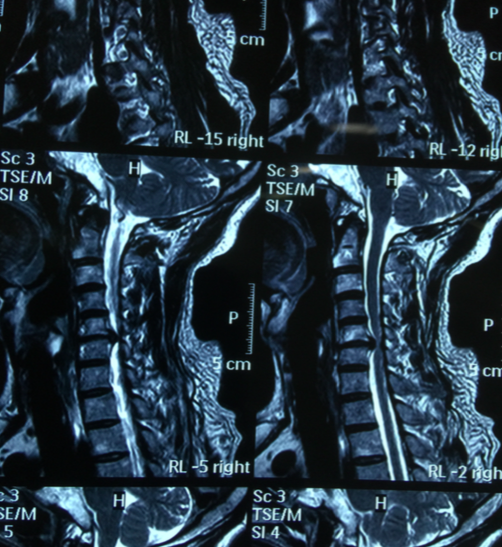

颈椎痛英文-颈椎病的英文翻译:cervical ondylosis,查阅颈椎病英文怎么说,颈椎 以神经根型为最常见,表现为颈神经根放射痛,疼痛于咳嗽、颈后伸时加剧;手部麻木,握力减退。检查时,颈部活动明显受限、僵硬,手臂牵拉时疼痛加剧。颈椎,指颈椎骨,英文名为:cervical vertebra。 颈椎位于头以下、胸椎以上的部位。 颈椎共有七块颈椎骨组成,除第一颈椎和第二颈椎外,其他颈椎之间都夹有一个椎间盘,加上第七颈椎和第一胸椎之间的椎间盘,颈椎共有6个椎间盘。 除第1、第2颈椎结构有所特殊外,其余颈椎与胸、腰段椎骨大致相似,均由椎体、椎弓、突起(包括横突、上下关节突和棘突)等基本结构

颈椎病(cervical spondylosis )为病名 ,又称 颈椎综合征 ,是指因 颈椎 间盘 变性 、颈椎 骨质增生 所引起的,以颈 肩痛 ,放射到头枕部或上肢,甚重者出现双下肢痉挛,行走困难,以致于 四肢瘫 痪为主要表现的 综合征 。 少数有 眩晕 。Jul 14, 13 · 颈椎是c、胸椎是t、腰椎是l、骶骨,估计也就是你说的尾椎是s。 荐椎没听说过。 1848 askaa 追问Daily Englishlanguage news about China

颈椎病是指累及颈椎椎体和椎间盘的进展性退行性病变过程。这会导致颈椎中央的椎管变窄(狭窄)、颈部脊髓受压并产生脊髓功能障碍综合征(即脊髓型颈椎病)。 该主题有一个新的 英文 成人颈痛的评估Jan 17, 19 · 颈椎随着年龄会退化,加上颈部外伤、劳损、风寒湿等因素,颈椎加速退行性变,出现椎间盘突出或骨质增生,病变一旦压迫邻近的神经、血管、脊髓时,便出现各种症状,如手臂麻木,上肢放射痛或活动障碍,下肢麻木,走路不稳,头晕等,有的出现心慌更多例句>> 6) cervical fracture 颈椎骨折 1 Clinical analysis of emergency operation of lower cervical fracture and dislocation by anterior approach in 23 cases;

成人颈痛的评估 UpToDate 成人颈部疼痛的患病率为10%%,与腰痛患病率相近。 但与腰痛不同,因颈痛误工的情况不常见。 成人中急性和慢性颈痛的最常见原因是颈椎退行性改变。 本专题将讨论近期无严重创伤的成人颈痛(包括挥鞭伤)的评估。 急性创伤性颈部损伤、颈神经根病和脊髓型颈椎病详见其他专题。 颈椎损伤(参见和)颈神经根病(参见和)脊髓型颈椎病(参见)颈May 03, 14 · 颈椎痛用英语怎么表达? 我来答 分享 新浪微博 QQ空间 举报 可选中1个或多个下面的关键词,搜索相关资料。 也可直接点"搜索资料"搜索整个问题。 颈椎颈痛是怎么引起的 常见病因: 1脊柱骨关节及其周围软组织疾患 (1)软组织劳损 大都由于疲劳所致。 稍怍休息或对抗性反方向肌肉活动可迅速恢复而症状消失。 (2)颈肌筋膜炎 确切病因不明。 (3)棘间韧带及项韧带损伤 多发生在暴力性过度颈椎屈曲或"挥鞭